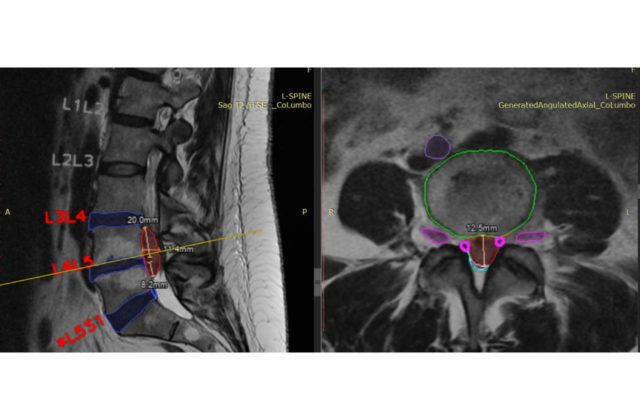

26.4.2023 (SITA.sk) – Unilabs, popredný poskytovateľ diagnostických služieb, nadviazal partnerstvo so spoločnosťou SmartSoft Healthcare s cieľom využiť jej riešenie CoLumbo, ktoré využíva umelú inteligenciu. Chce tak v Španielsku dosiahnuť zlepšenie popisovania a vyhodnocovania vyšetrenia driekovej chrbtice pomocou magnetickej rezonancie.

CoLumbo skracuje rádiológom čas popisovania a vyhodnocovania nálezom o 25 %, zvyšuje počet vyšetrených pacientov a zároveň zlepšuje presnosť diagnóz. Klinické testy dokázali, že CoLumbo môže znížiť počet chýb z opomenutia až o 15 %.